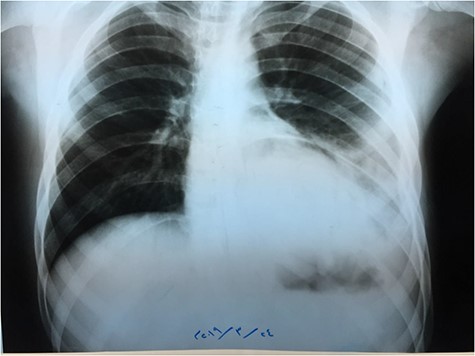

A catheter was placed and fluid infusion began, and emergency thoracentesis showed fresh blood. Immediate exploratory thoracotomy was performed (Fig. 3). Three liters of blood were extracted, and the pleural adhesions were liberated. A diaphragmatic hernia was found, with an ischemic strangulated and perforated stomach. The stomach was freed, found vital, its perforation was repaired and it was returned to the abdominal cavity. The opening in the diaphragm was sutured and supported with the omentum. The lung was in good shape.